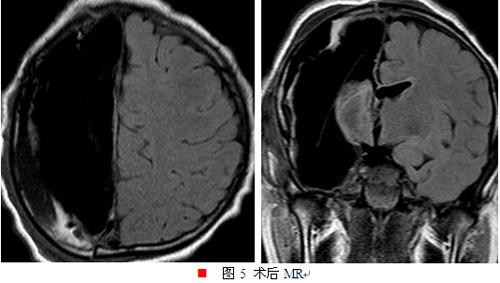

经我院癫痫中心讨论后考虑患者右侧大脑半球为致痫区,可行右侧大脑半球切除术,经患者及其家属沟通后同意手术,遂于2016年8月18日行右侧大脑半球切除术,术后肢体功能同术前无差别,且现患者术后近2月余,无癫痫发作,精神状态及智能较术前明显改善。